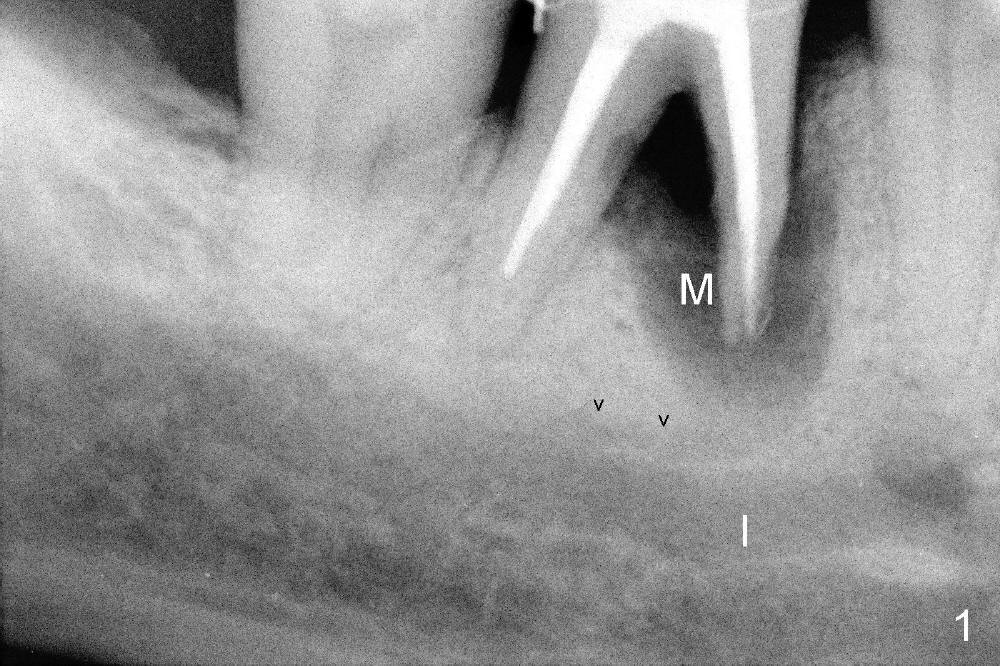

The tooth #30 of a 64-year-old man has endo failure with large radiolucency in the mesial socket (Fig.1 (PA), 2 (CT)).  The tooth is nonsalvageable.  The mesial lesion is closer to the inferior alveolar nerve (I/IAN) than the distal apex.  In addition, there is a connection (Fig.1,2 arrowheads and Fig.2 insert pink dashed line) between the mesial lesion and the nerve.  What is the connection, as related to extraction and immediate implant?

There are three potential spaces for the immediate implant: the mesial and distal sockets and the septum.  First at all, the tooth should be extracted with curettage of granulation tissue from the mesial apical lesion.  The latter turns out to be difficult, since the bottom of the mesial socket has abrupt transition into a narrow neck, which look and feels like the IAN.  To determine the depth of the lesion relative to the IAN, PA is taken (Fig.3) without too much information.  When a radiopaque material in placed in the mesial socket (Fig.4 M), the lesion has apparently not extended to the IAN.  Curettage of the remaining granulation tissue is now an easy task.  Finally bleeding comes from a small hole, as indicated by arrowhead.  Therefore the special structure is a branch of the inferior alveolar vessels.